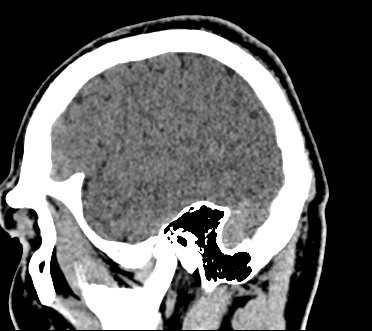

Методика построена на использовании проникающей способности рентгеновских лучей, которые в различной степени поглощаются органами и тканями (степень поглощения зависит от их плотности), благодаря чему можно получить подробные изображения внутренних органов. Во время исследования трубка томографа вращается вокруг пациента и производит снимки поперечного сечения, что позволяет детально визуализировать кости черепа и все структуры головного мозга.

Наши медицинские центры оснащены новейшими мультиспиральными компьютерными томографами экспертного уровня TOSHIBA AQUILION в различных модификациях. Аппараты снабжены увеличенным количеством сверхчувствительных детекторов, что позволяет при сканировании выполнять от 64 до 128 срезов поперечного сечения с минимальной толщиной среза от 0,5 мм. В результате получаются изображения исследуемой зоны в мельчайших подробностях, которые затем с помощью инновационных цифровых приложений преобразуются в трехмерные пространственные модели головного мозга для более точной диагностики.

Нативное сканирование подходит для диагностики дистрофических изменений головного мозга, определение острого нарушения мозгового кровообращения, как ишемического, так и геморрагического характера, а также отслеживание последствий подобных состояний при прохождении реабилитации.